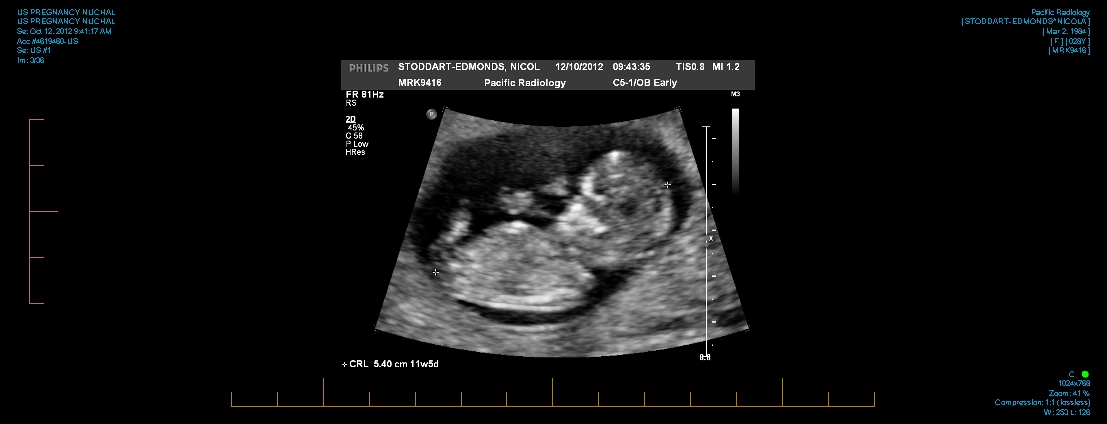

Attachment 6768 Hi all! Any guesses?? thanks x

not sure if its the nub im seeing, if it is maybe boy